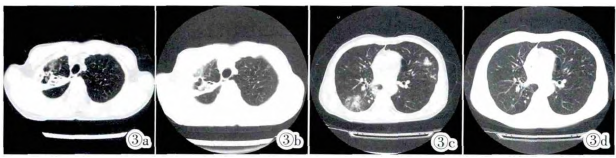

临床诊断:播散性NTM病(①NTM肺病;②左腕NTM骨病)。药敏实验后改用A、Lfx、Clr、Rfbcfz抗NTM治疗。治疗2月后患者咳嗽及关节肿痛减轻,肺部见好转(图3),破溃皮肤愈合,腕关节活动无障碍。

图3 抗NTM后右肺下叶及左肺上叶病灶明显吸收好转,右肺上叶病灶改变不明显,右肺上叶空洞形成。